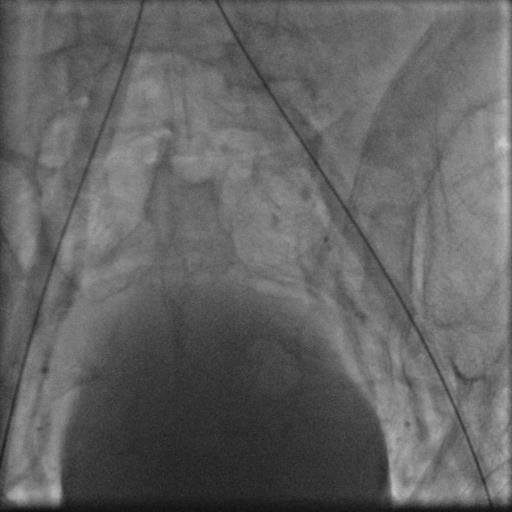

56 yaşında şeker, böbrek yetmezliği ve tansiyon hastalığı olan hastamız yol yürürken baldırlarında ağrı,ayaklarda his kaybi,sogukluk,cinsi zayıflık şikayetleriyle bize IRAK' tan başvurdu .Hastamızın bu şikayetleri 6 aydan beri giderek artmaktaymış.Yaptığımız detaylı muayeneler sayesinde hastamızın böbrek damarlarının ayrıldığı, hizanın altından aort damarının tamamen tıkalı olduğunu tesbit ettik. Aortik Tıkanma (Leriche Sendromu) teşhisi koyuğumuz hastaya yaptığımız başarılı stentleme işleminden sonra tam akım sağlanarak 3 gün sonra şikayetlerinde azalmayla taburcu edilmiştir.